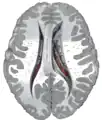

Transverse Cut of Brain (Horizontal Section), basal ganglia is blue | |

Ventricles of brain and basal ganglia. Superior view, horizontal section, deep dissection

Ventricles of brain and basal ganglia. Close-up of preceding image